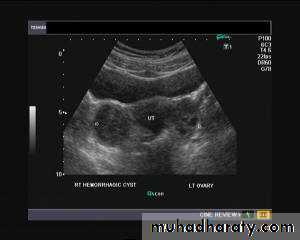

Hemorrhagic ovarian cysts:

Hemorrhagic cyst of ovary resulting from Ovulation induction

This young nulliparous female patient undwerwent ultrasonography following ovulation induction. The right ovary shows a typical hemorrhagic cyst formed from the corpus luteum. The first image (top row- left) is a transabdominal ultrasound image showing fine fibrinous strands within the cystic mass in the right ovary. Transvaginal ultrasound and color Doppler images confirm these findings. The uterus shows typical secretory changes in the endometrium suggesting post ovulatory phase.